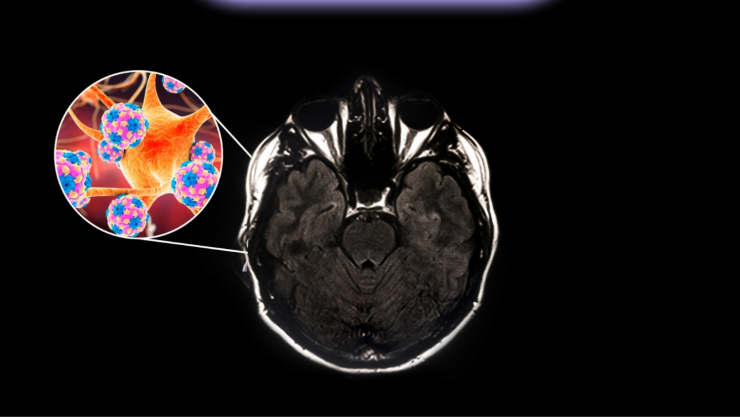

La meningitis bacteriana es una infección grave que provoca la inflamación de las membranas que rodean el cerebro y la médula espinal, conocidas como meninges. Se trata de una enfermedad que puede avanzar rápidamente y poner en riesgo la vida si no se atiende a tiempo.

Entre los síntomas más comunes se encuentran fiebre alta, dolor de cabeza intenso, rigidez en el cuello, vómito y sensibilidad a la luz. En casos graves, puede causar complicaciones neurológicas o la muerte en poco tiempo.